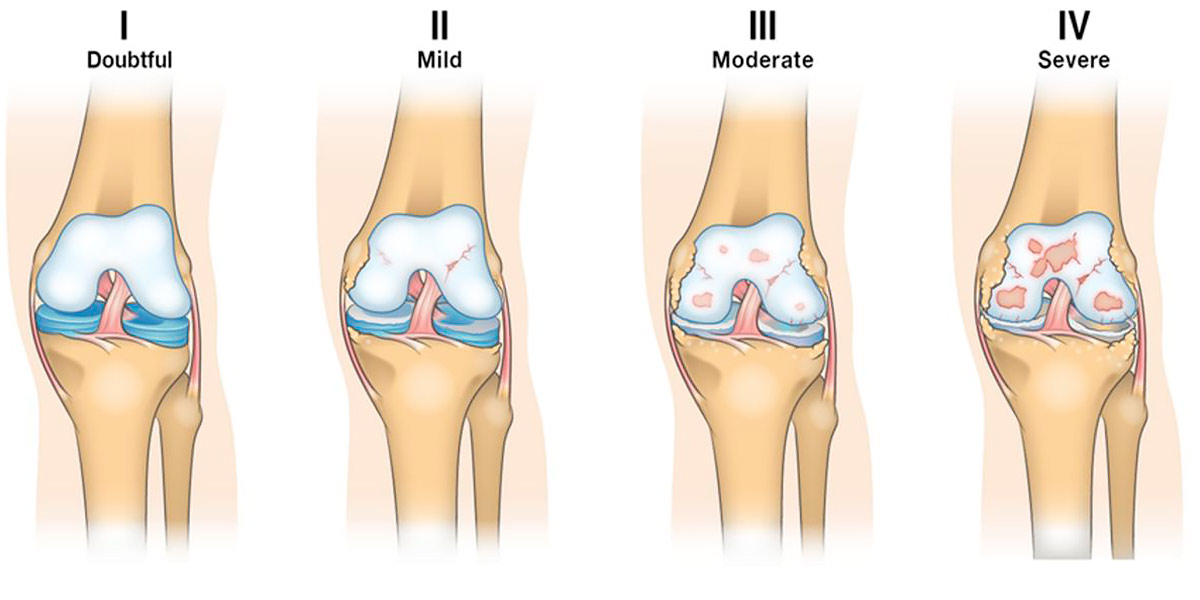

O joelho de corredor é um síndrome que aparece quando pela utilização excessiva continuada a cartilagem articular se degrada (às vezes a dor começa a surgir antes de começar este processo), causando a exposição do osso por degradação das estruturas protetoras e danificando a medula óssea devido ao atrito provocado entre a rótula e o fémur.

Figura II. Graus I-IV de lesão na cartilagem da articulação do joelho.

Este quadro define o joelho de corredor como uma alteração estrutural, habitual em praticantes de desporto de idade média-avançada, e, inclusive, também em não praticantes de desporto, muitos deles idosos que podem sofrer este quadro simplesmente por degradação das articulações com o passar do tempo (Petersen et al., 2014).

Só deve ser utilizada em casos muito concretos, como por exemplo nos graus III e IV de osteoartrite, pelo que nos jovens está totalmente desaconselhado recorrer à cirurgia, a menos que um especialista faça a sua avaliação e o defina como a orientação mais recomendada a seguir para o tratamento.